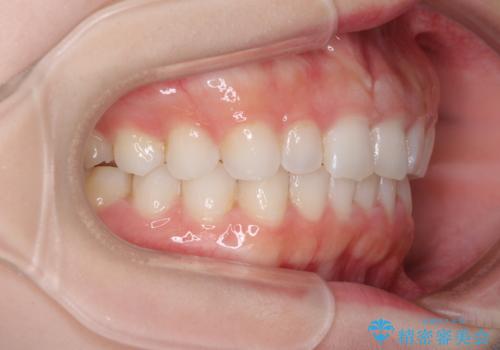

デコボコと深い咬み合わせの改善 インビザラインによる矯正治療

インビザラインによる上下歯列の拡大と、IPR(歯と歯の間を削る)にるスペースの獲得により、口元のデコボコとディープバイトを改善することとしました。

インビザラインは、装着していない時間がどれだけ短いかが、治療期間を大きく左右します。こちらの患者様は1日22時間以上、毎日欠かさず装着してくださったため、1年強という短期間で満足のいく歯列に整えることができました。